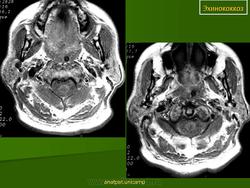

Патоморфология. Эхинококк — пузырь с довольно толстой слоистой хитиновой оболочкой, наполненный прозрачной жидкостью, содержащей янтарную кислоту. Различают эхинококк однокамерный и многокамерный, или альвеолярный. Эхи'нококк вызывает в мозге реактивное воспаление, что приводит к образованию плотной капсулы, наружные слои которой инфильтрированы лимфоидными, плазматическими и эозинофильными клетками. Располагается он чаще всего в глубине полушарий. Величина эхинококка колеблется от горошины до куриного яйца. В некоторых случаях он растет кнаружи и, выходя на поверхность мозга, может узурировать кость.

Клиника эхинококка напоминает клинику опухоли головного мозга. При нем бывает выражен гипертензионный синдром, сочетающийся с очаговыми симптомами. Характерные изменения развиваются в костях черепа: они истончаются над эхинококком и в отдельных случаях могут разрушаться, открывая опухоли выход наружу. Эхинококковый пузырь в этих случаях прощупывается на поверхности черепа в виде плотной флюктуирующей опухоли. В крови эозинофилия. В ликворе бывают положительные белковые реакции, небольшой эозинофильный плеоцитоз, янтарная кислота.